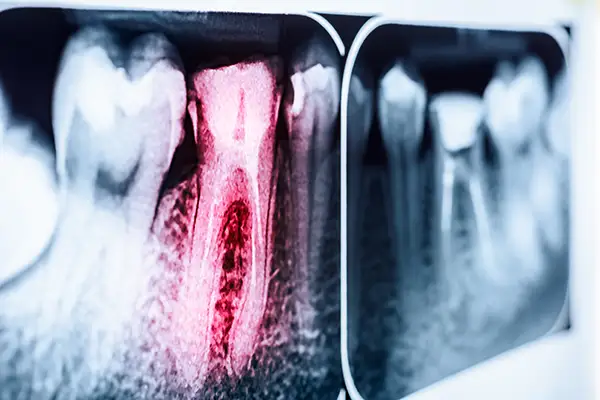

Dental X-ray highlighting an infected tooth root canal with inflammation in red.Endodontic Retreatment gives a second chance to teeth where a previous root canal didn’t fully resolve the problem. Our endodontist carefully reopens the tooth, removes the prior filling material, identifies what went wrong, and retreats the canals to promote proper healing.